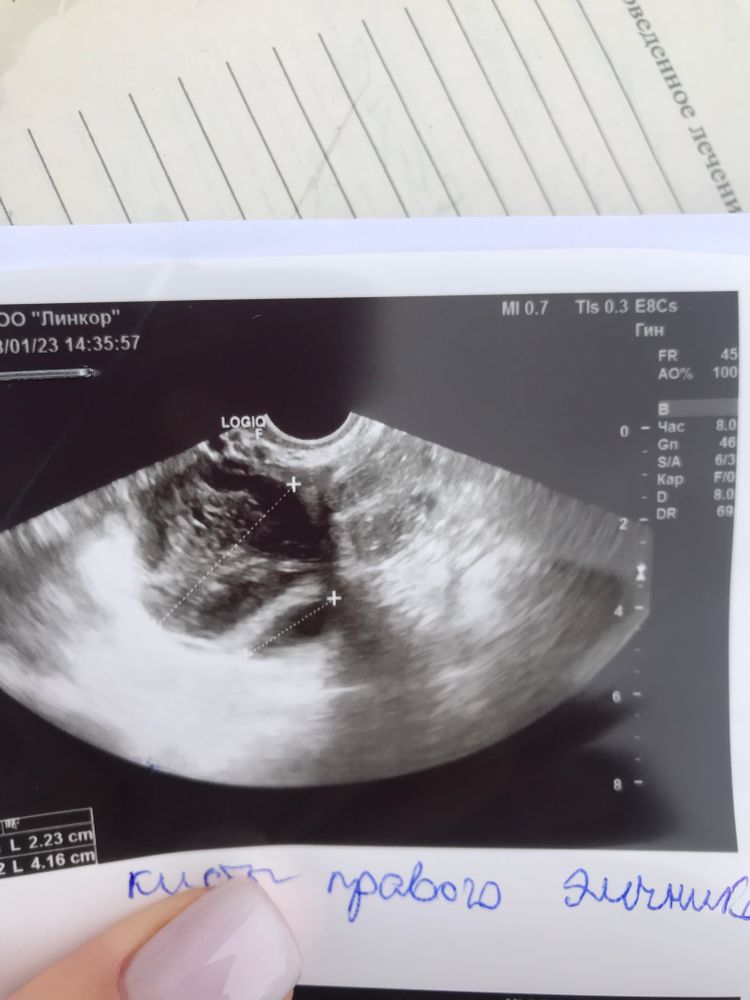

Здравствуйте. Была на узи 4 дня назад, был 1 дф 21,6мм, пошла на узи снова из-за болей в боку, оказалось две кисты жт 2см и 4см…как так быстро выросли и что делать? Сегодня 20-тый день цикла после чистки зб.

Это слишком резко восстановился цикл не просто желтое тело, а кистозное. Не волнуйтесь они уйдут без лечения. После месячных их уже не будет